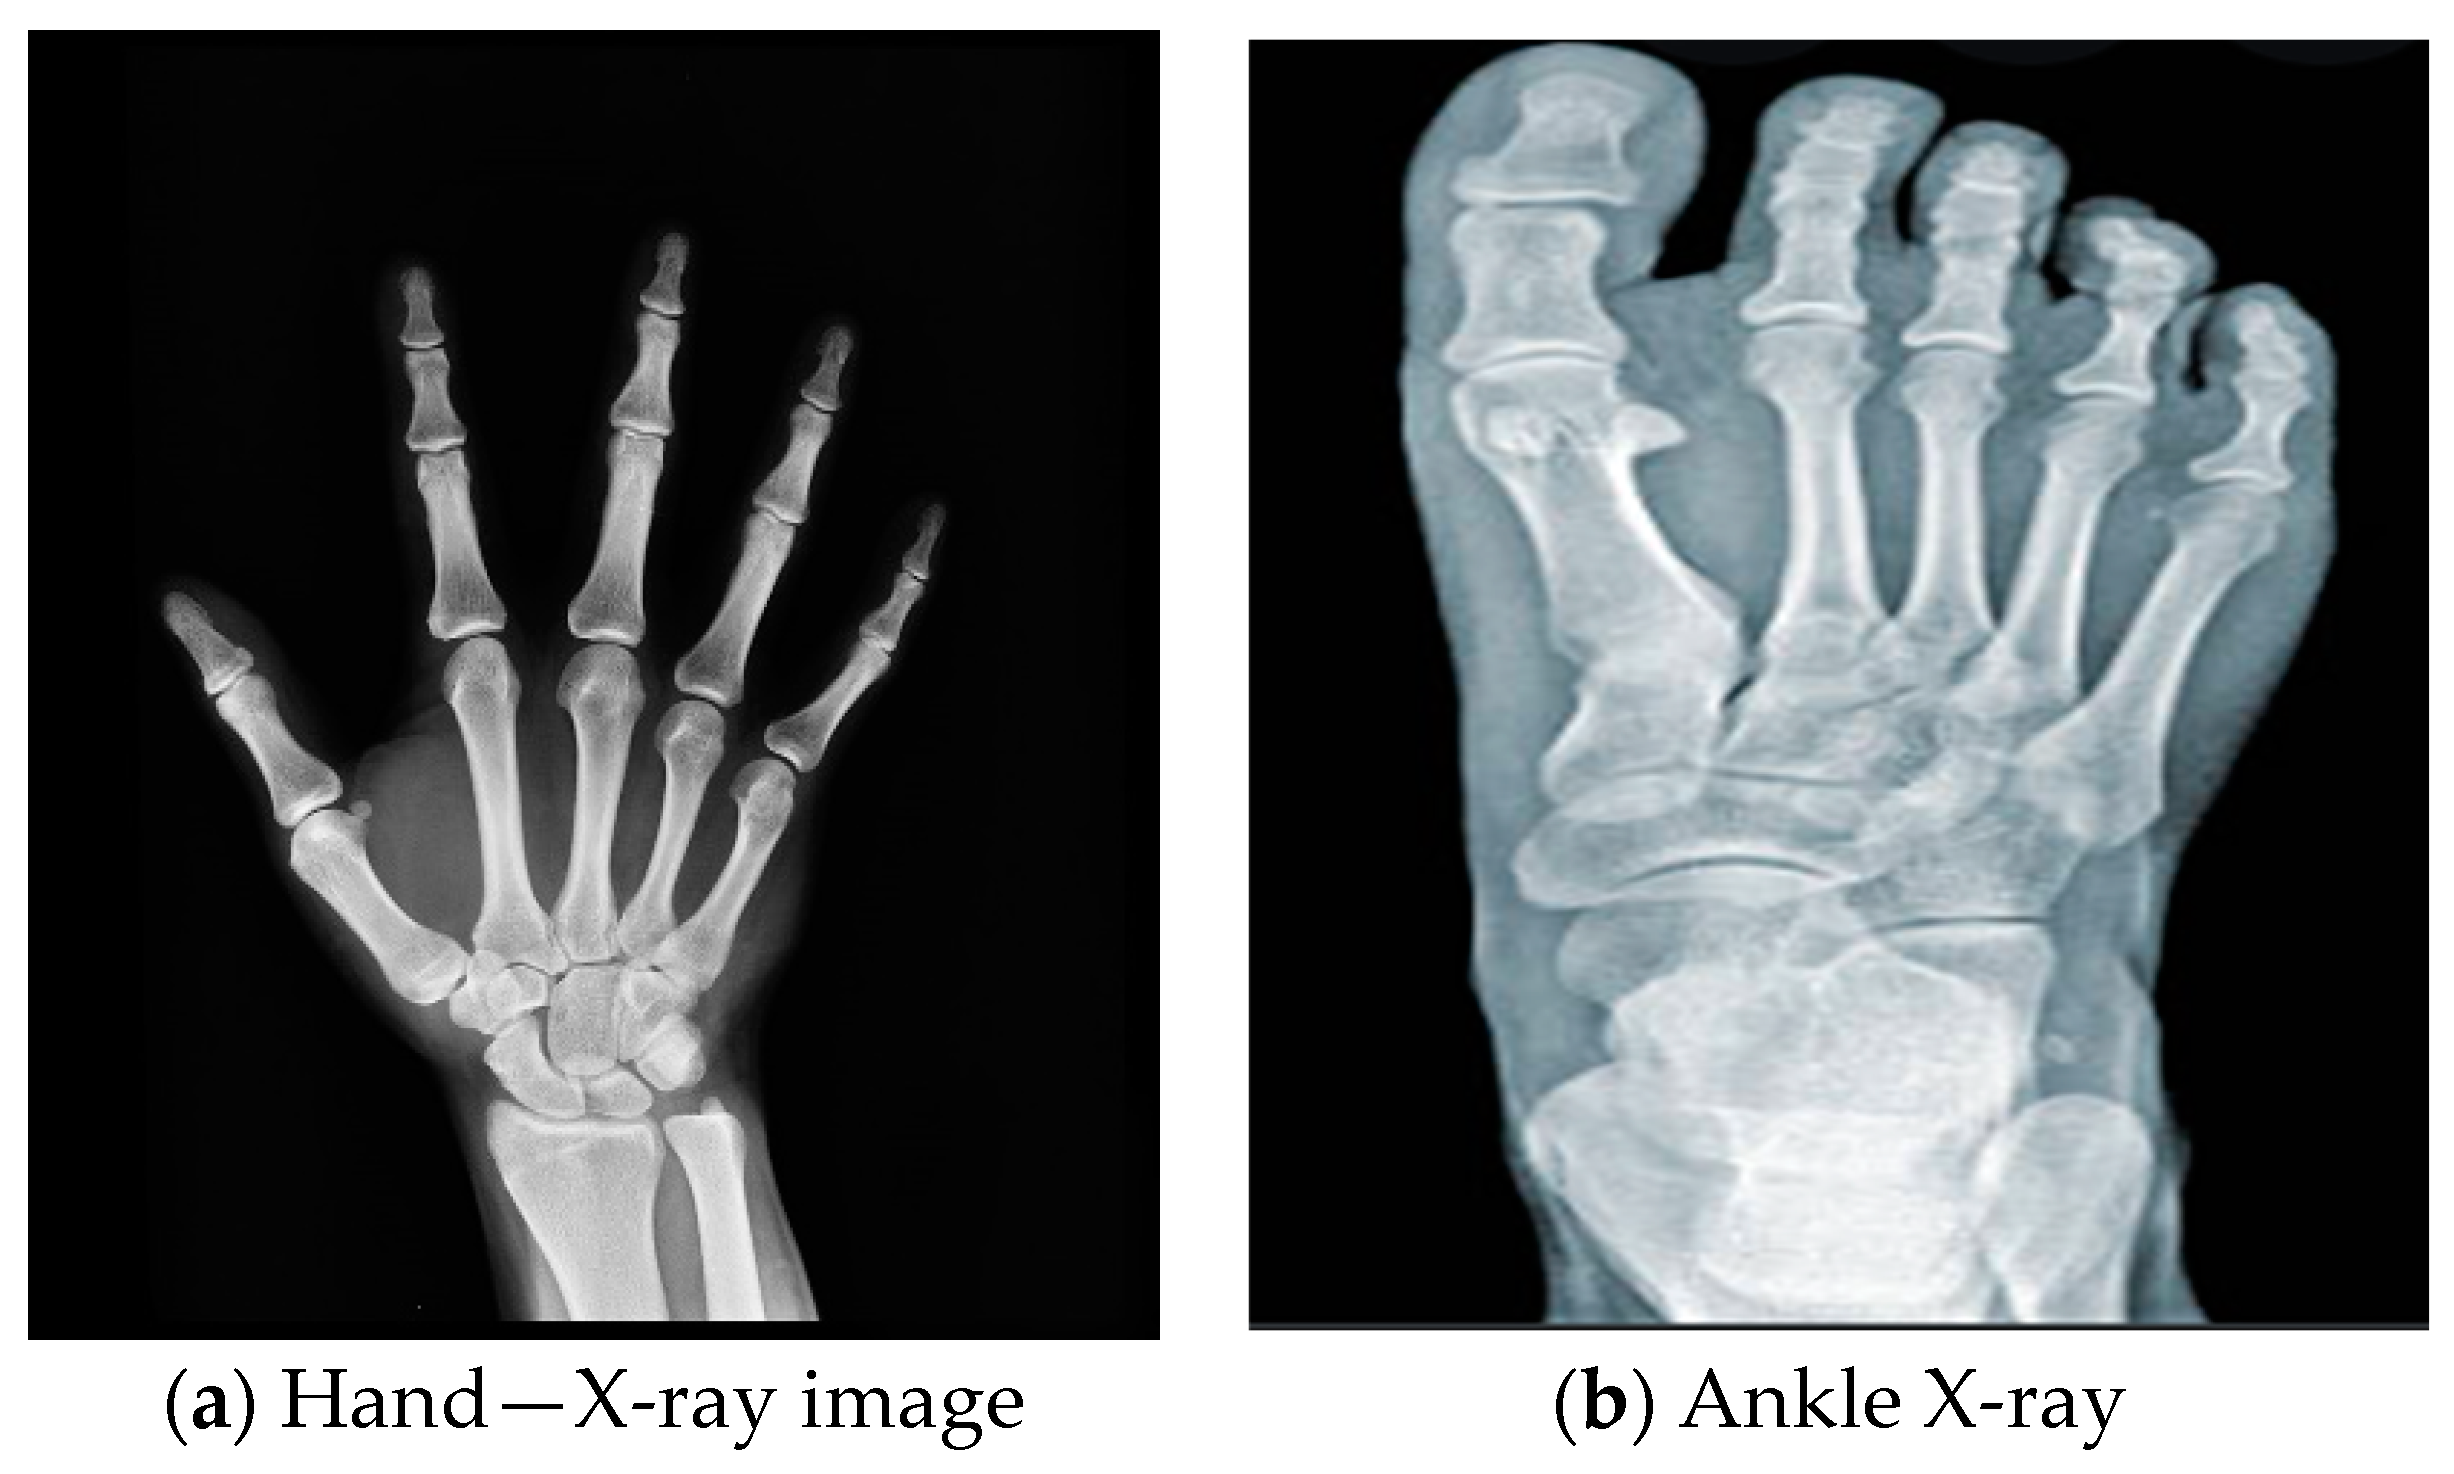

PACS stands for Picture Archiving and Communication System. PACS is a computerized system for storing, retrieving, and managing medical pictures. It gives healthcare practitioners easy access to a patient’s entire imaging history [13,14]. Examples of X-ray images are shown in Figure 1.

Figure 1.

X-ray images.